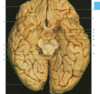

Label the arteries that supply A-C [3]

A

A = anterior cerebral artery (upper

and medial parts of the cortex)

(orange)

B = middle cerebral artery (lateral

areas of the frontal, parietal, and

temporal lobes) (white)

C = posterior cerebral artery (occipital

lobe and inferior parts of the

temporal lobe) (blue)